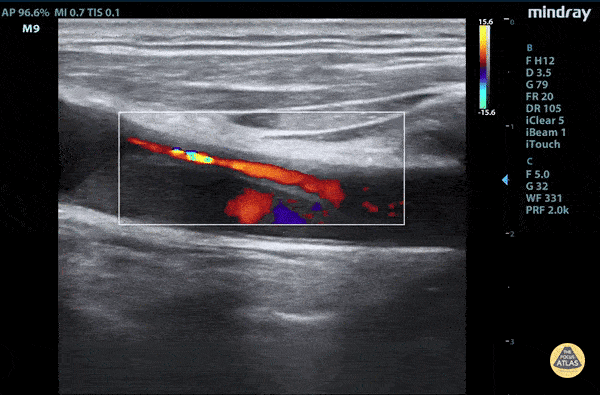

Aorta - Aortic dissection flap tamponade color flow

Elderly fellow who had a headache while bike riding, with some leg weakness. No chest or back pain. Stable for hours then came to hospital, suddenly hypotension and drowsy in ER POCUS RUSH Exam performed lead to rapid diagnosis of Aortic Dissection with tamponade. A dissection flap can clearly be visualized with color flow around it. Claire Heslop - Pediatric Emergency Medicine - University of Toronto Hospital for Sick Children